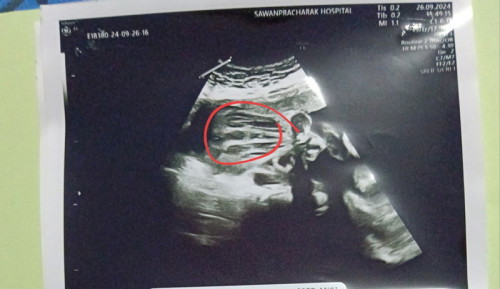

คืออยากสอบถามแม่ๆๆค่ะ พอดีตอนซาวด์น้องตอน 25 week แต่น้องดันหนีบขาไว้ไม่ยอมอ้าออก เรยไม่แน่ใจว่าน้องเป็น ญ หรือ ช แม่ๆท่านไหนพอจะมองออกไหมค่ะ ขอความคิดเห็นหน่อยค่ะ